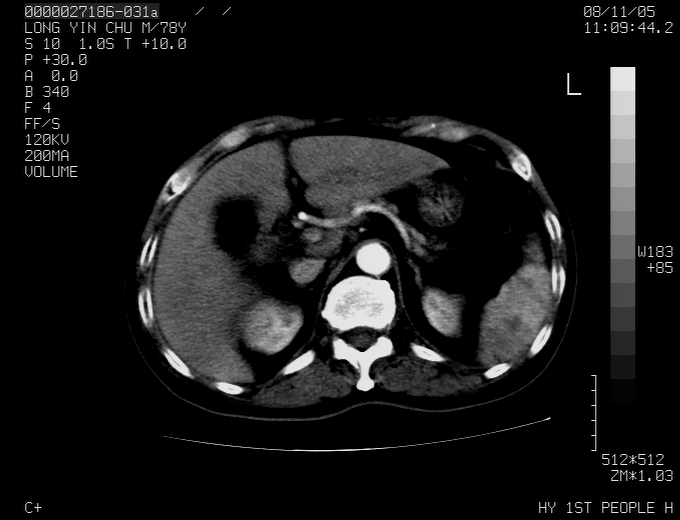

标题: CT16532:M78Y,肝脏病变,请会诊 [打印本页]

标题: CT16532:M78Y,肝脏病变,请会诊

腹胀,腹痛就诊,男性,78岁,外院b超未见异常。

肝ca,脾肾转移

支持脾肾转移瘤,双侧胸腔积液。

考虑弥漫性肝癌并脾及双肾转移.双侧胸水.

图片质量欠佳:多考虑:左侧肾癌。脾脏转移!胸膜转移!

肝脾肾转移瘤可能性大,左肾不除外梗塞,双侧胸水

考虑弥漫性肝癌并脾及双肾转移,双侧胸水。

考虑肝癌并双肾及脾脏转移;双侧胸腔积液。